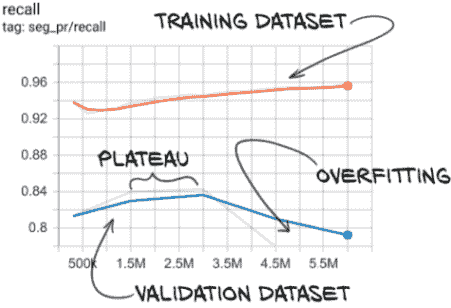

我们所看到的是过拟合的明显迹象。让我们看一下我们在正样本上的损失图,见图 12.18。

图 12.18 我们的正损失显示出明显的过拟合迹象,因为训练损失和验证损失趋势不同。

在这里,我们可以看到我们的正样本的训练损失几乎为零–每个正样本训练样本都得到了几乎完美的预测。然而,我们的正样本的验证损失却在增加,这意味着我们的实际表现可能正在变差。在这一点上,最好停止训练脚本,因为模型不再改进。

提示 通常,如果您的模型在训练集上的表现正在提高,而在验证集上表现变差,那么模型已经开始过拟合。

然而,我们必须注意检查正确的指标,因为这种趋势只发生在我们的正损失上。如果我们看一下我们的整体损失,一切似乎都很好!这是因为我们的验证集不平衡,所以整体损失被我们的负样本所主导。正如图 12.19 所示,我们在我们的负样本中没有看到相同的发散行为。相反,我们的负损失看起来很好!这是因为我们有 400 倍的负样本,所以模型要记住个别细节要困难得多。然而,我们的正训练集只有 1,215 个样本。虽然我们多次重复这些样本,但这并不会使它们更难记忆。模型正在从泛化原则转变为基本上记住这 1,215 个样本的怪癖,并声称不属于这几个样本之一的任何东西都是负样本。这包括负训练样本和我们验证集中的所有内容(正负样本都有)。

图 12.19 我们的负损失没有显示过拟合的迹象

显然,仍然存在一些泛化,因为我们大约正确分类了 70%的正验证集。我们只需要改变我们训练模型的方式,使我们的训练集和验证集都朝着正确的方向发展。

然而,问题在于我们的召回率(因此也是真正的正例率)。我们的召回率在第 5 到 10 个时期之间趋于平稳,然后开始下降。很明显,我们很快就开始过拟合,我们可以在图 13.18 中看到更多证据–虽然训练召回率继续上升,但验证召回率在 300 万个样本后开始下降。这就是我们在第五章中识别过拟合的方式,特别是图 5.14。

图 13.18 验证集召回率,在第 10 个时期后显示出过拟合的迹象(300 万个样本)

注意 请始终记住,TensorBoard 默认会平滑您的数据线。实色背后的浅色幽灵线显示了原始值。

U-Net 架构具有很大的容量,即使我们减少了滤波器和深度计数,它也能够很快地记住我们的训练集。一个好处是我们不需要训练模型很长时间!